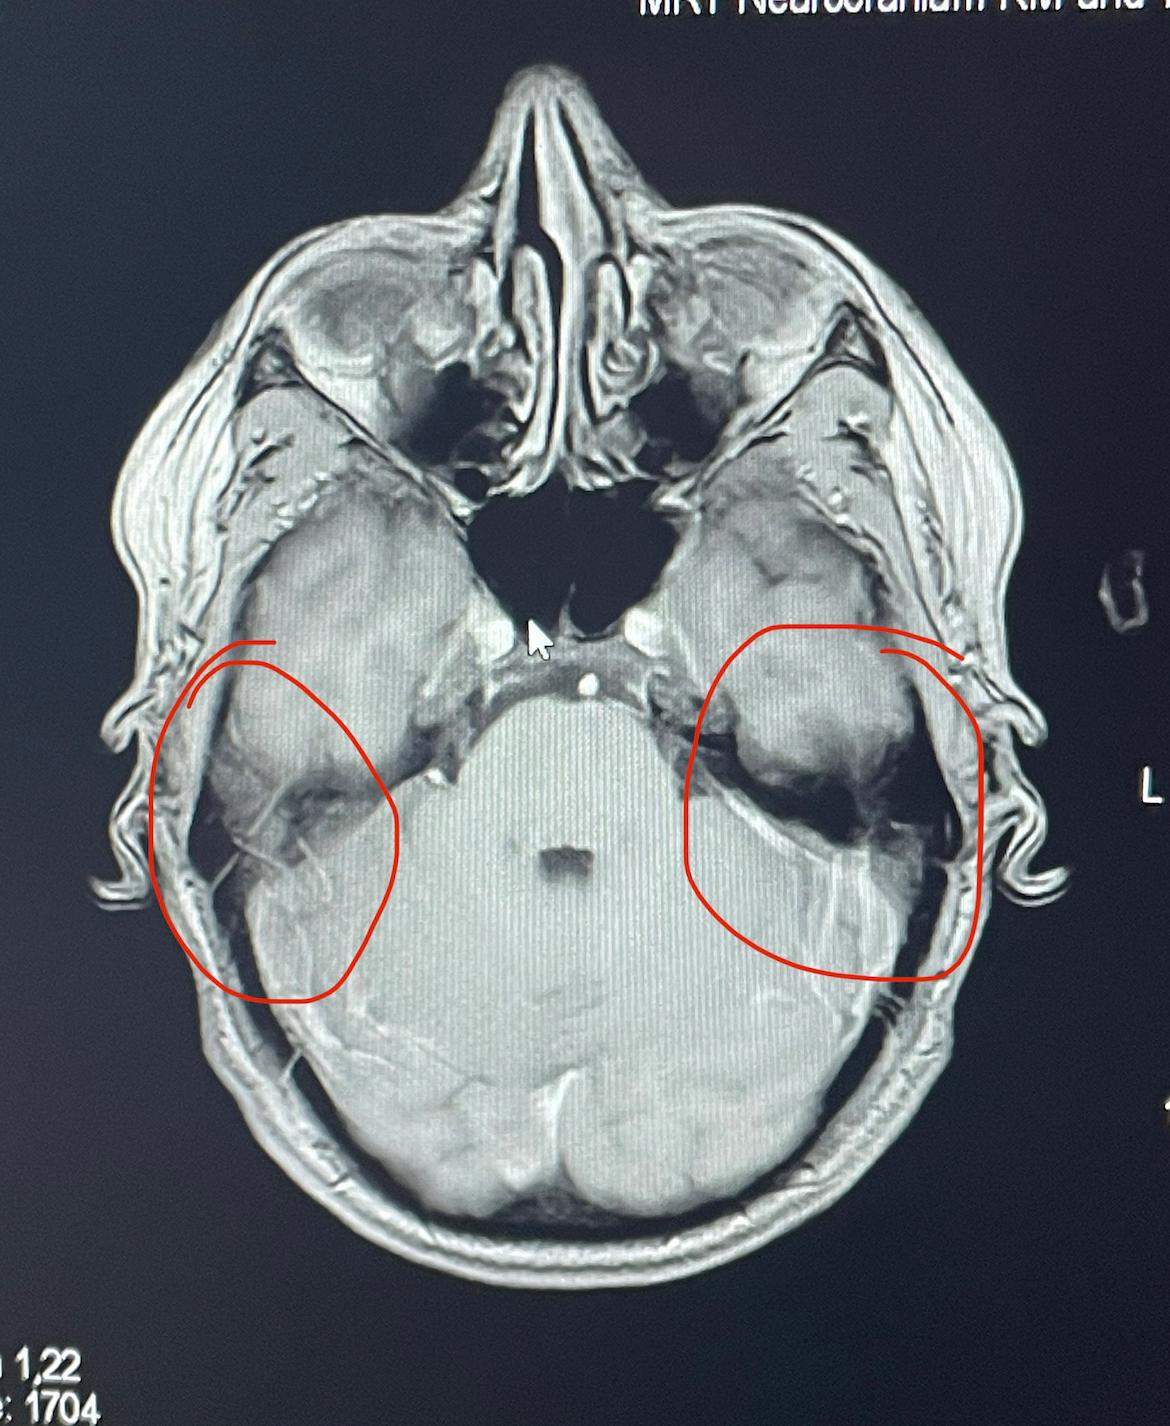

MRT Befund Schädel. Ungleich, normal? (Gesundheit und Medizin)

Was sagt dieser MRTBefund vom Kopf aus? (Gesundheit und Medizin, Gesundheit, Medizin)

MRT Schädel, was ist das? (MRT Befund, Kontrastmittel)